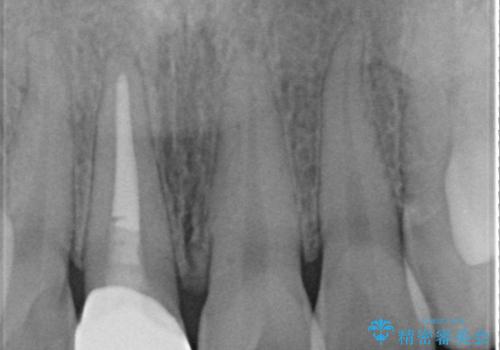

- 患者様は、他院にて5年前に前歯の神経をとってから、変色が気になり出したとのことでご来院されました。

セラミックのみも可能でしたが、念のため根管治療からのやりかえをご希望されました。

根管治療について

保険根管治療は回数がかかることが多く、終了予定がわかりにくいです。

当院では、根管治療は長い時間のご予約を頂き、多くの場合2~3回で終わります。

根管治療は歯内の治療なので患者様には見えない場所ですが、ここが細菌で汚染されると激しい痛みや長引く違和感の原因になります。

当院では、清潔な治療を徹底し、顕微鏡を使用した精密な治療を行っています。

症状や根管の状態により、治療金額が異なります(5~10万円目安)。治療回数による費用負担の増減はありません。